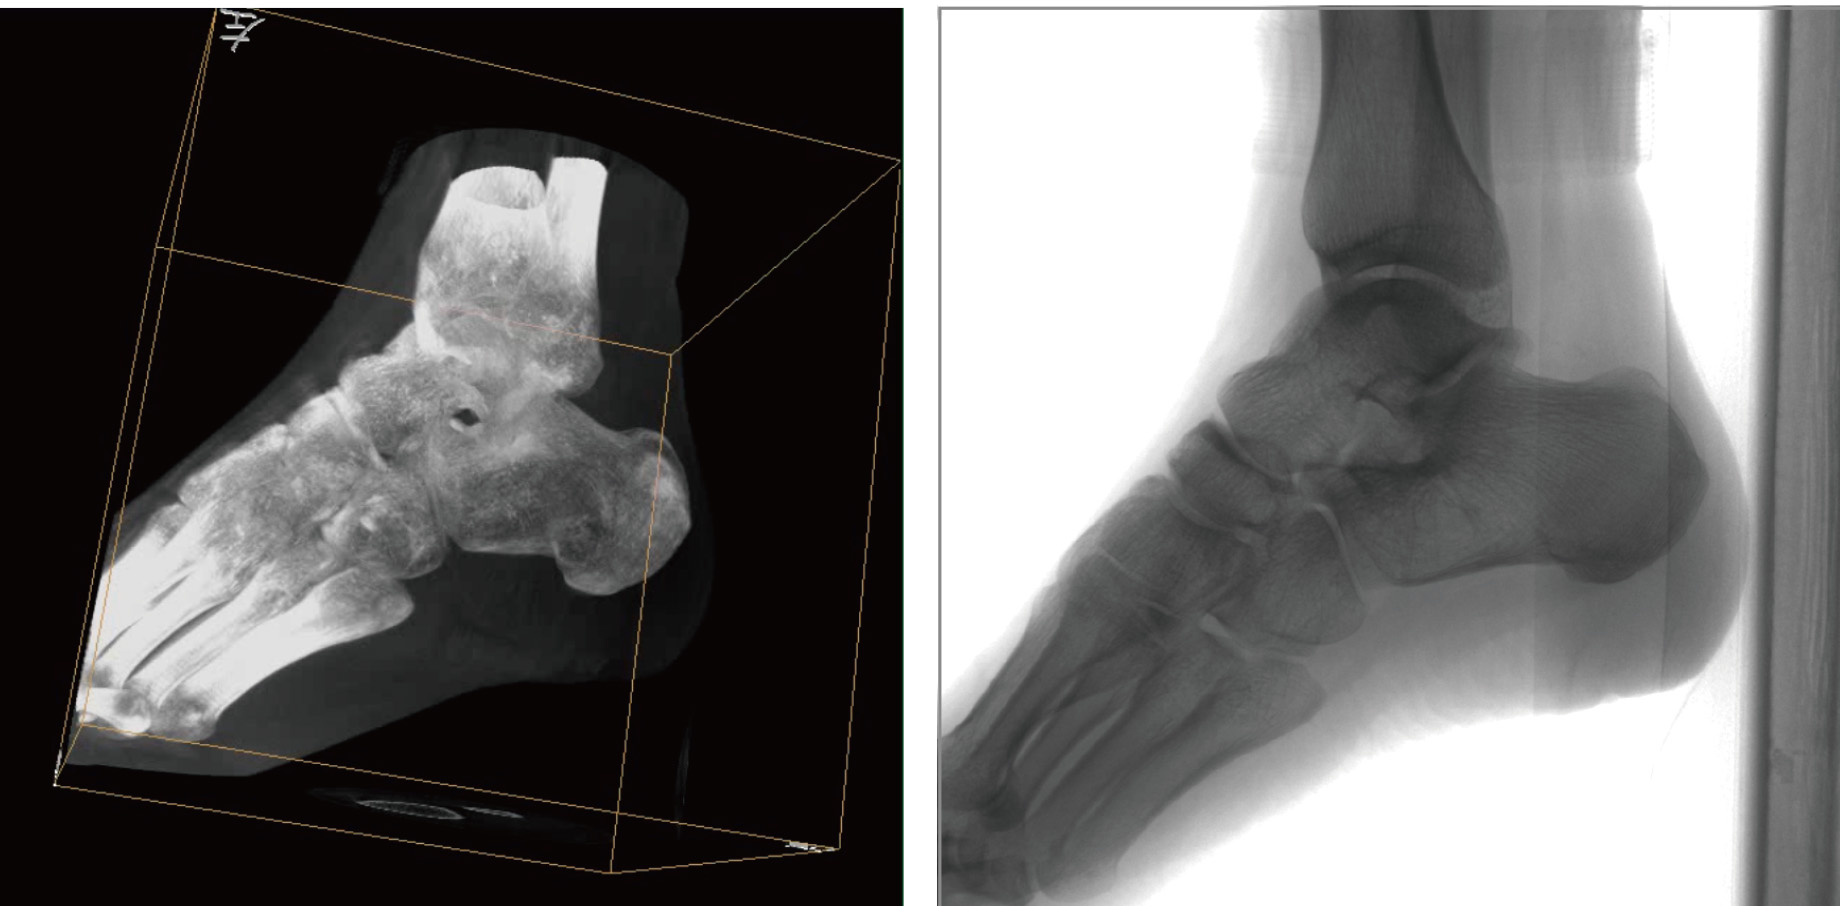

普愛醫療天弓PLX7500骨科三維C形臂,作為“術中CT”,在手術中快速生成類CT斷層圖像和立體三維圖像,為醫者提供更全面的圖像信息,能夠準確地觀察植入物的情況,例如螺釘內固定術入釘的位置和角度。天弓PLX7500三維C形臂性能特點:

PLX7500骨科三維C形臂通過采集,能在術中快速地生成橫斷面、矢狀面、冠狀面和可旋轉的立體圖像,給術者提供360°無死角的觀察角度,準確判斷骨組織和植入物的情況,為手術的實施提供保障,極大提高手術成功率,減少并發癥概率。